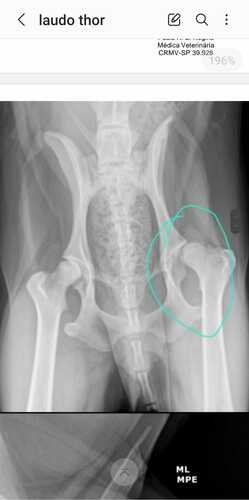

Eu me chamo Franciny e recentemente nosso cachorrinho Thor machucou a patinha e irá precisar de cirugia. O valor para gente é muito alto no momento e impossível de pagar, nosso cachorrinho está sentido muita dor e precisa dessa cirugia urgente. Por favor pessoal nos ajude com qualquer valor.